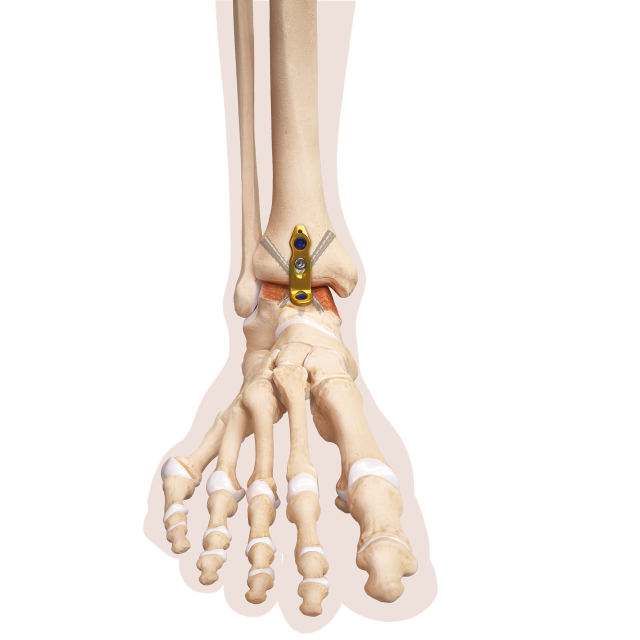

Ist die Knochenqualität schlecht, kann die Stabilisierung mittels winkelstabiler Plattensysteme vorgenommen werden.

Um das Weichteilrisiko möglichst gering zu halten, kann die Operation in arthroskopischer Technik vorgenommen werden). Dies reduziert den postoperativen Heilungsverlauf, benötigt aber ein hohes Maß an chirurgischer Erfahrung. Für diese Technik sind spezielle kleine Plattensystem entwickelt worden, um eine zusätzliche Stabilisierung erreichen zu können, falls die Knochenqualität eine stabile Fixierung mittels zweier Schrauben nicht zulässt.